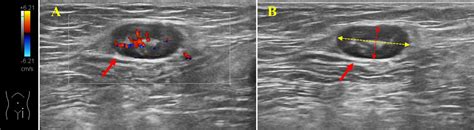

During a consultation, your physician will likely perform a physical examination to check the size, texture, and location of the node. They may also order blood tests, imaging studies such as an ultrasound, or in some cases, a biopsy to determine the exact cause of the swelling. Early diagnosis is key to effective management, regardless of whether the cause is a simple infection or something requiring more intensive treatment.